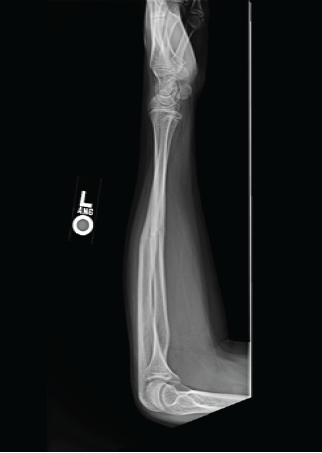

Radiographic evaluation of the left forearm showed a healed both-bone forearm fracture with good alignment (Fig. 2 and 3).

Figure 2: Lateral view X-ray demonstrating well healing both bones.